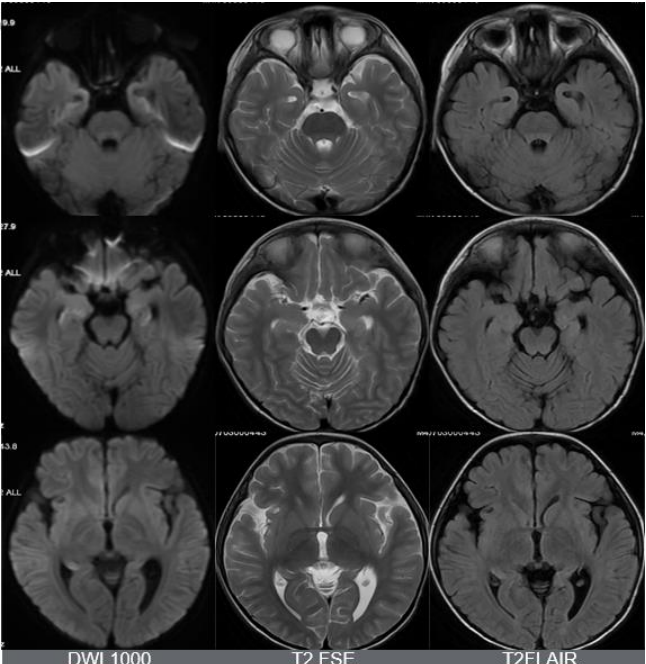

MUSE DWI 1000,168 × 264,提示双侧额叶皮层弥散受限。

除此之外,海马的信号怪怪的,是什么?所以,我们加扫海马矢状位小视野弥散。

海马最外层呈弥散受限表现,但是总感觉雾里看花,并不清晰。我们还能做什么?